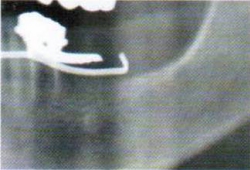

腐食して壊れた義歯

機能回復のため保険義歯を駆使して作り替えつづけて、結果的に溶けてしまった下顎骨(9年後)